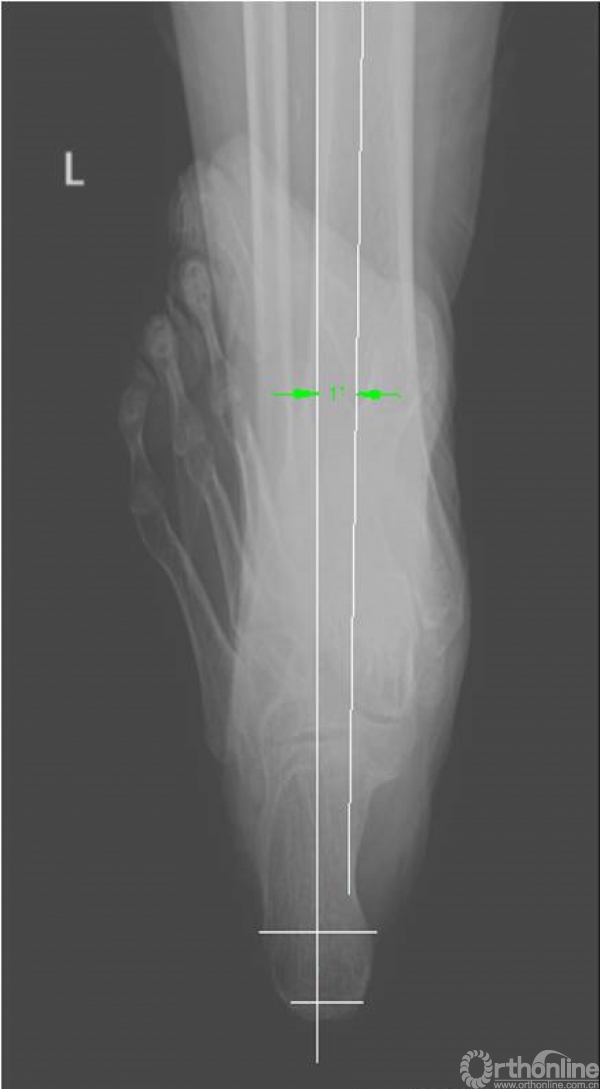

3. X线检查结果

X线检查